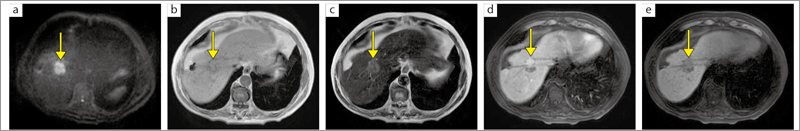

■症例2:TAE(肝動脈塞栓療法),RFA(ラジオ波焼灼療法)施行後の残存病変(肝細胞がん)検索

肝S8に拡散強調画像で高信号域(a),T1強調in-phase画像で低信号域(b),T2強調画像で約30mmの淡い高信号域を認める(c)。Gd-EOB-DTPA造影MRIを施行し,動脈相で残存病変の濃染区域を認める(d)。肝細胞造影相では,肝S8の残存病変は低信号域として描出されている(e)。後日CTガイド下で肝S8の残存病変に対しRFAを再度施行した。

a:DWI,DWI-EPI,TR/TE:5500/70,マトリックス:128×128,FOV:400mm,スライス厚:5mm,撮像時間:3分00秒

b:T1W1 in-phase,GE,TR/TE:165/4.6,マトリックス:320×192,FOV:350mm,スライス厚:8mm,撮像時間:21秒

c:T2WI,FSE,TR/TE:5500/120,マトリックス:288×244,FOV:350mm,スライス厚:8mm,撮像時間:17秒

d:TIGER(3D),RSSG(delay 30sec),TR/TE/FA:4.0/1.7/15°,マトリックス:256×224,FOV:380mm,スライス厚:5mm(2.5mm)

e:TIGER(3D),RSSG(delay 20min),TR/TE/FA:4.0/1.7/15°,マトリックス:256×224,FOV:380mm,スライス厚:5mm(2.5mm)